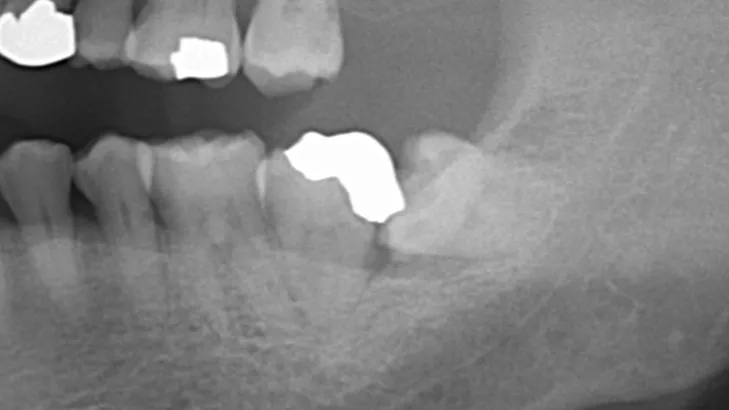

今回は目視で親知らずに虫歯が確認できるほかにレントゲン撮影やCT撮影で歯の方向や不良補綴物をしっかり確認🤩

レントゲンからも手前の歯の詰め物が引っかかっているので、親知らずの円滑な抜歯のためには、手前の歯の詰め物除去が同時に必要なことが分かりました😌